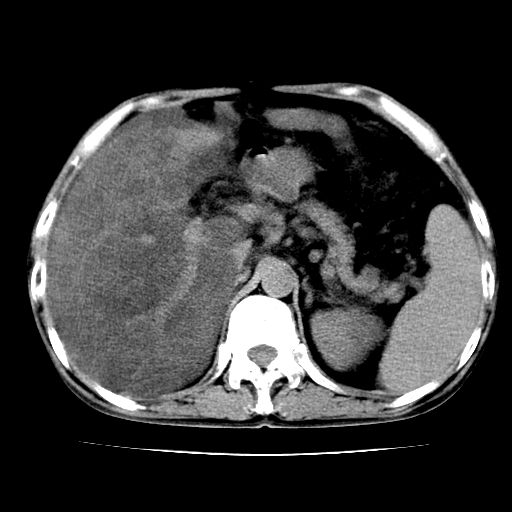

男,55岁,发现“肝硬化”5年,现腰疼、腹胀10余日,巩膜黄染、腹稍胀,肝肋下3指,质硬无压疼,移动性+,血生化:总胆、直胆、间胆均升高。

g1:肝硬化、脾大、腹水。

2:脂肪肝。

3:弥漫性肝癌待排。

肝硬化,脾大,腹水

脂肪肝

肝内多发低密度灶(建议增强扫描除外肝癌)